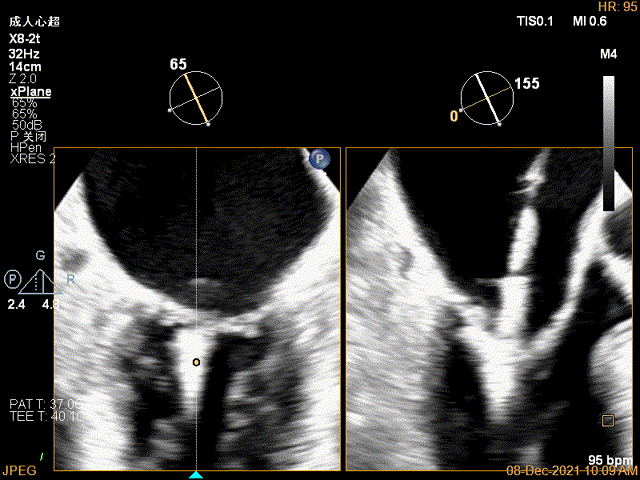

第一个夹子放置侯二尖瓣口平均跨瓣压差:4mmHg

肺静脉血流频谱恢复正向

x-plane验证前后叶抓捕后bond明显